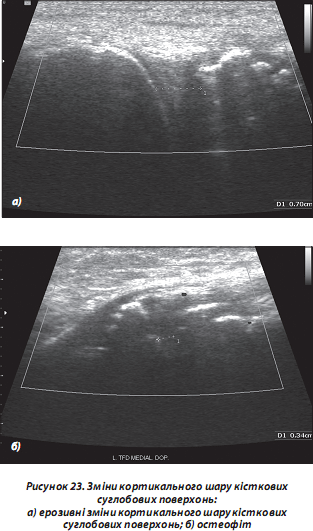

г) зміни кортикального шару кісткових суглобових поверхонь (ерозивні, дегенеративні, зокрема остеофітоз; пухлинні ураження; патологія періосту, у тому числі при остеомієліті; переломи/тріщини тощо) (рис. 23);